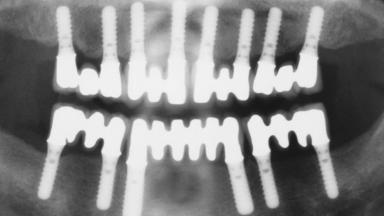

Immediate Loading of Eight Implants in the Maxilla and Six Implants in the Mandible and Final Restoration with Three-Unit and Four-Unit FDPs